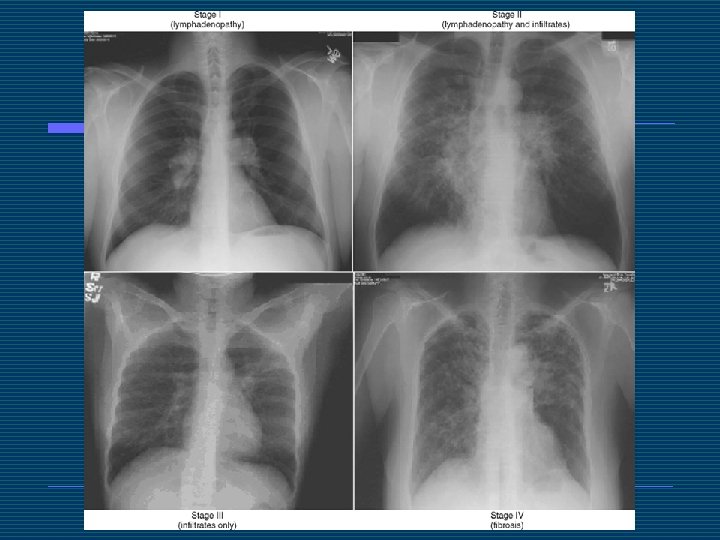

Solunum Sistemi o o Akciğer tutulumu %90’ın üzerindedir. Öncelikle parankim tutulur. Sıklıkla asemptomatiktir. Dispne, kuru öksürük, göğüs ağrısı olabilir.

o o Lenf nodu tutulumu, hava yolu lezyonları (larinks, trakea, bronş), %20 hastada astım benzeri duruma yol açabilir. Plevral tutulum nadirdir. Bilateral olarak eksudatif efüzyon olabilir.